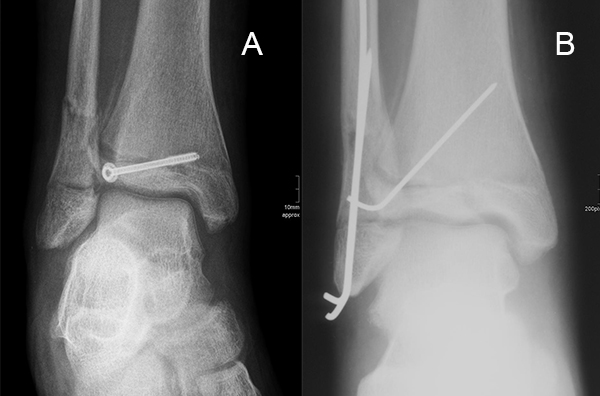

Ist die korrekte Stellung nur gegen einen federnden Widerstand zu erreichen, kann die Fraktur durch perkutane K-Drähte stabilisiert werden. Bei einer Fugenschaftfraktur mit großem Keil ist auch eine Schraubenosteosynthese möglich (Abbildungen 13 bis 14).

Behandlungsziel ist die exakte Rekonstruktion der Gelenkfläche sowie die Minimierung des Risikos einer späteren Wachstumsstörung. Dislozierte Frakturen werden offen reponiert, die Osteosynthese erfolgt mit einer Kleinfragmentschraube. Finden sich viele kleine Fragmente kann eine K-Draht Osteosynthese durchgeführt werden. Wird der Innenknöchel operiert, kann bei gleichzeitiger hochgradiger lateraler Instabilität eine Rekonstruktion des lateralen Bandapparats durchgeführt werden. Fibula Frakturen stellen sich meist spontan ein, sodass hier keine zusätzliche Osteosynthese notwendig ist.

Dislozierte Frakturen (Frakturspalt > 2 mm) werden grundsätzlich operativ behandelt. Die Reposition kann arthroskopisch unterstützt erfolgen. Die Schraubenosteosynthese erfolgt entsprechend dem Frakturverlauf. Bei Twoplain Frakturen ist meist eine epiphysäre Schraube ausreichend die von lateral kommend das Fragment nach medial-proximal fixiert. Der Schraubenverlauf ist üblicherweise von lateral ventral nach proximal dorsal medial (Abb. 24). Nach Reposition darf in der seitlichen Aufnahme des Sprunggelenks, als auch in der 45° Außenrotationsaufnahme keine Stufe in Höhe der Wachstumsfuge erkennbar sein. Eine sichtbare Stufe ist Indikator für eine unzureichende Reposition.

Bei Triplane-Frakturen fasst die metaphysäre Schraube das metaphysäre Fragment einschließlich eines hinteren Volkmann Dreiecks, die epiphysäre Schraube fasst das epiphysäre Fragment. Da der Fugenschluss noch nicht abgeschlossen ist, sollten die Schrauben die Wachstumsfuge nicht kreuzen, obwohl eine Wachstumsstörung unwahrscheinlich ist (v. Laer 2013).